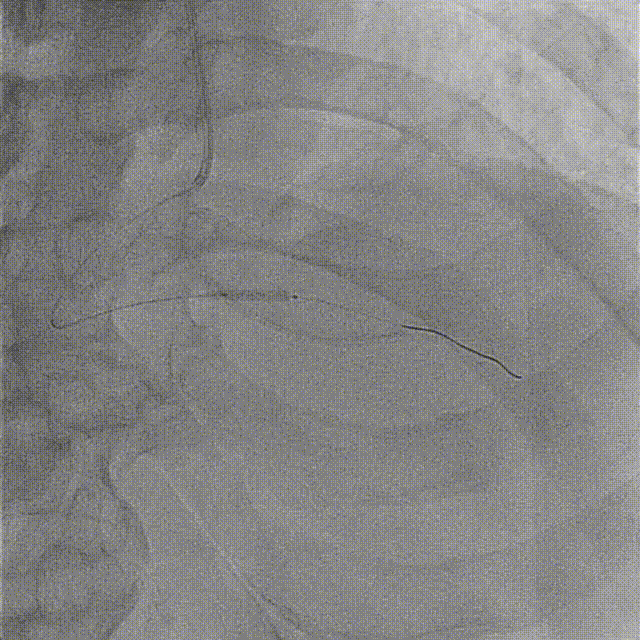

复查造影见右冠血流通畅,无明显残余狭窄及夹层影

远期随访中患者无自觉症状,血压心率稳定。